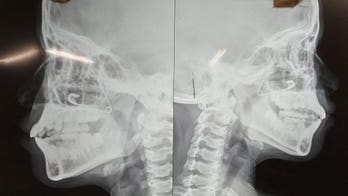

September 11, 2018 Missouri boy, 10, survives being impaled in the face by a metal meat skewer A Missouri father said his 10-year-old son is lucky to be alive after the child was impaled by a 12-inch metal meat skewer when he fell from a tree house.